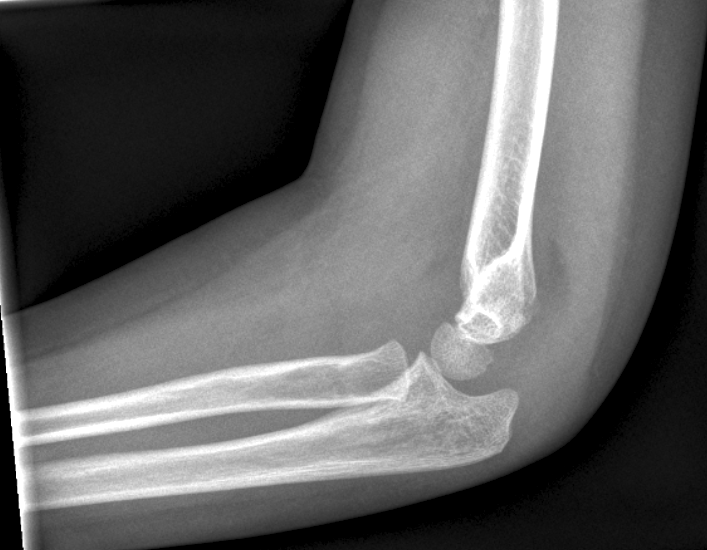

Se efter intra artikulær ansamling (prøv at stille på

kontrasten så bliver det tydligere):

Dislocerede (se figur) frakturer behandles med reposition og osteosyntese med 2

Dislokation: En linie langs forsiden af humerus går normalt igennem midterste

1/3 del af capitulum humeri. Hvis hele capitulum ligger bagved denne linje skal

der reponeres og osteosynteres i GA. Hos børn under 4 år tillades lidt større